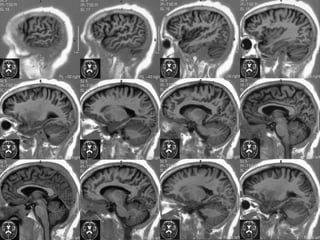

Divisão anatômica cerebral

Superfície medial

• Separadas pela fissura cerebral longitudinal,

• Unidas em algumas partes pelas comissuras,

e estruturas que limitam o III ventrículo.

CORPO CALOSO

• Maior comissura cerebral,

• Principal parte do teto dos ventrículos laterais,

• Joelho , Corpo , Esplênio e Rostrum.

• 10cm de comprimento / 2,5 cm de altura.

TRÍGONO OU FÓRNIX

• Pilares anteriores , corpo e pilares posteriores.

• Corpo teto do III ventrículo,

abaixo       tela coróidea

• Anterior se curva até os corpos mamilares,

CORTE MEDIANO

• MESENCÉFALO

– TETO

– PEDÚNCULO

• PONTE

• BULBO (OBEX, CLAVA)

• MEDULA ESPINHAL

• VERMIS CEREBELAR (TODOS OS

LÓBULOS E FISSURAS)

• IV VENTRÍCULO - VALÉCULA